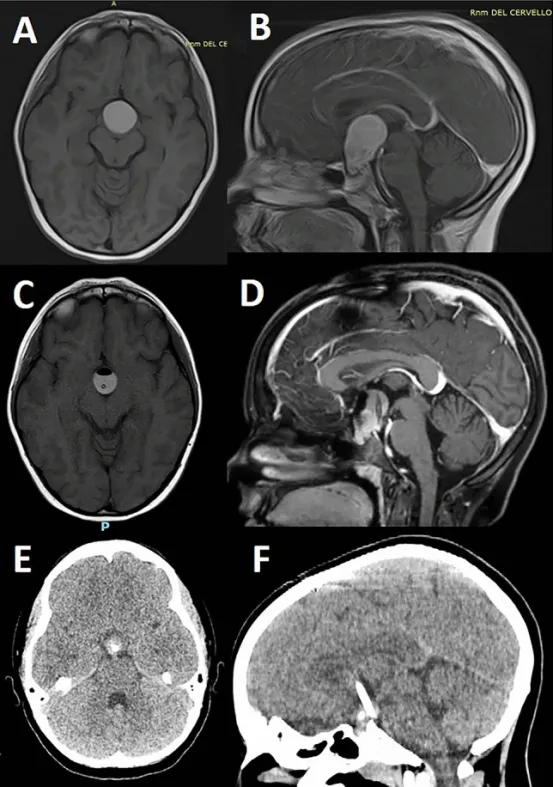

7岁女性患儿的T1加权MRI平扫(图A)及增强扫描(图B)显示颅咽管瘤(AC)。增强后可见肿瘤实性部分强化,囊性成分呈典型表现。

介入治疗后影像(图C、D):导航引导下放置囊内导管并抽吸出典型"机油样"囊液后,复查MRI显示囊肿体积显著缩小,周围受压结构(如视通路、第三脑室)获得有效减压;囊壁仍可见残留强化,但占位效应明显缓解。

长期随访结果(图E、F):末次随访(4年后,完成3周期腔内治疗/IA后)CT扫描证实囊性成分基本消失,仅残留小型、钙化的鞍内肿瘤实性部分;未见囊肿复发或进展征象,提示病情长期稳定控制。